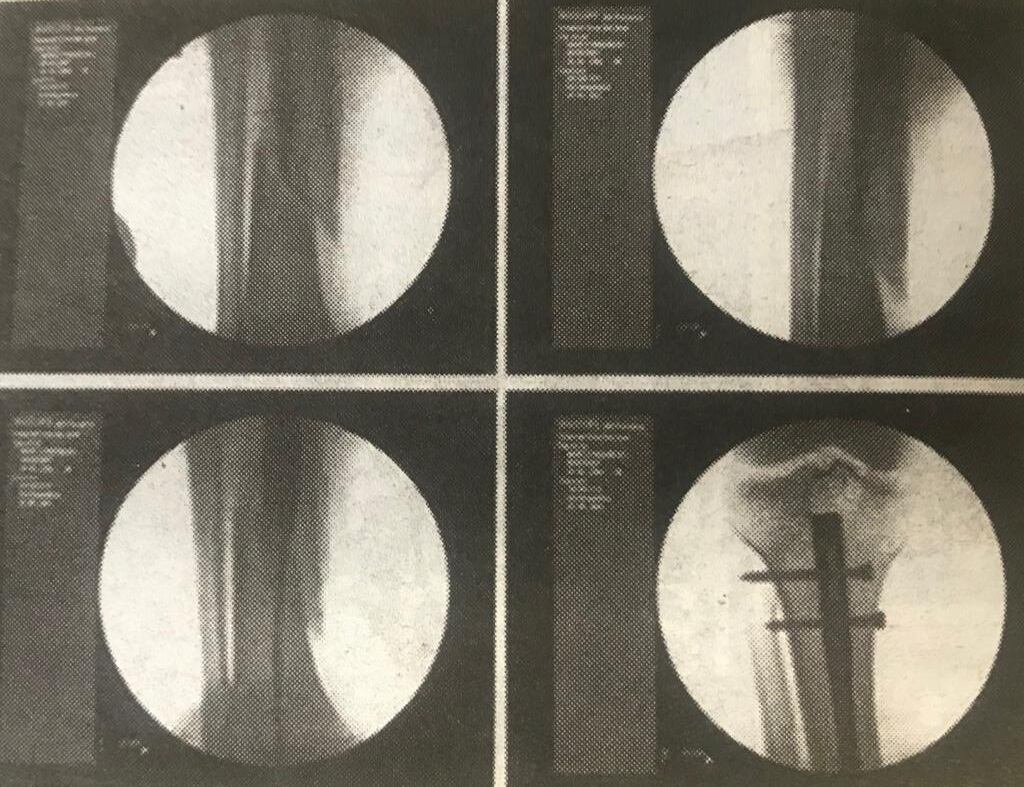

Don Marco sufrió una fractura de tibia y peroné, pero la Expo Pococí no activó ninguna póliza. Tampoco lo hizo la empresa Diversiones Stop, dueña de los juegos.

“Me tuvieron que poner un pin y pasé en cama casi tres meses, más otros seis en rehabilitación. Yo trabajo en lo propio y pasé muchos meses sin poder trabajar, ellos no se hicieron responsables, por eso decidí poner una demanda ante los tribunales. El juez me dio la razón y los obligó a que me pagaran, situación que no se ha dado 12 años después.